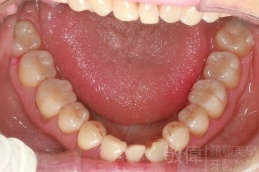

齒顏矯正/戽斗臉型 變身 大帥哥

矯正前-上   矯正前-下

矯正後-上   矯正後-下

<個案說明>

戽斗(學名第三級咬合 class III)矯正之後,戽斗的樣子就比較沒有了。最主要的改變是在牙齒的咬合。從側面比較,治療前、治療後的臉型 可更明顯看出來 戽斗的感覺 減少了很多。